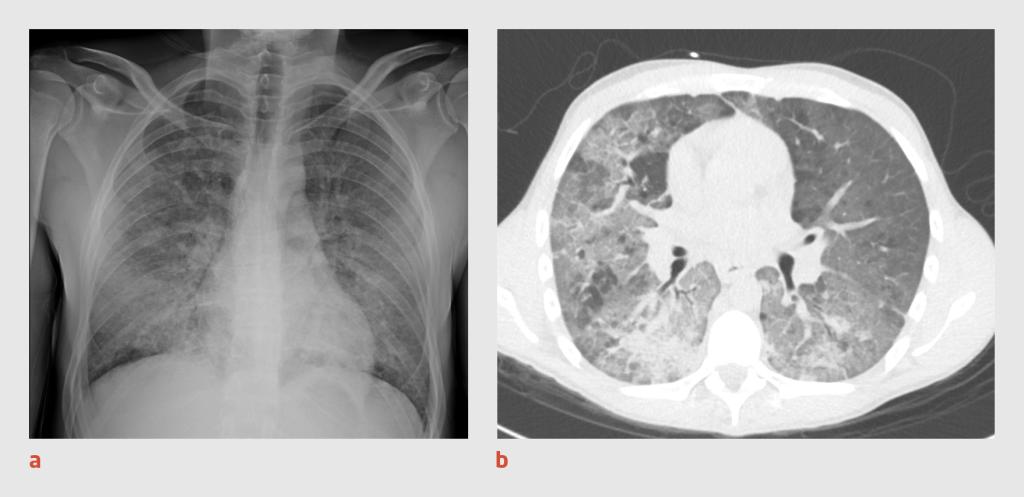

Figuur 3

Thoraxfoto en CT-thorax van patiënt C

Figuur 3 | Thoraxfoto en CT-thorax van patiënt C

(a) Thoraxfoto van een 71-jarige vrouw waarop in beide longen uitgebreide consolidaties te zien zijn. (b) Op de CT-scan van de thorax zijn uitgebreide peribronchovasculaire matglasafwijkingen met scherpe contouren (‘crazy paving’) en grillige consolidaties zichtbaar, overeenkomstig een CO-RADS-score van 5.

Er wordt een PCR-test verricht op SARS-CoV-2 in materiaal uit de nasofarynx en patiënte wordt intraveneus behandeld met ceftriaxon 2 g 1 dd. Ook krijgt zij digoxine voorgeschreven vanwege het nieuw ontstane atriumfibrilleren. Het urinesediment bevat 10-50 leukocyten/μl (< 10), > 150 erytrocyten/μl (0) en natrium 14 mmol/l (geen referentiewaarde, omdat de urinenatriumconcentratie onder andere wordt bepaald door het dieet). De nierinsufficiëntie wordt geduid als ‘prerenaal’ en passend bij een slechte vochtinname. Patiënte krijgt NaCl 0,9% 2 l/h toegediend per infuus. De volgende dag blijkt de uitslag van de PCR-test negatief te zijn. Omdat wij op basis van het klinische beeld nog steeds een vermoeden van covid-19 hebben, wordt CT-onderzoek van de thorax verricht. Op de CT-scan worden uitgebreide peribronchovasculaire matglasafwijkingen gezien met scherpe contouren (‘crazy paving’; CO-RADS-score 5) (figuur 3b); deze afwijkingen passen niet alleen bij covid-19, maar ook bij een P. jiroveci-pneumonie of een auto-immuunpneumonitis. Met een PCR-test konden in de bronchoalveolaire lavagevloeistof geen verwekkers, zoals SARS-CoV-2 of P. jiroveci, aangetoond worden. Vanwege het vermoeden van auto-immuunpneumonitis worden de concentraties van antinuclaire antistoffen (ANA) en antistoffen tegen het cytoplasma van neutrofiele granulocyten (ANCA) in het bloed bepaald.